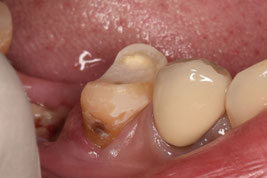

「日本よりも素晴らしい医療を受けることができそうなヨーロッパの国」から来院された方です。在住先の複数の歯科医院で右下5番の根管治療を断られたため、日本での治療を希望され来院されました。

右下6番も根管治療を断られてしまい、痛みが酷かったため抜歯したそうです。抜歯してからも強い違和感と腫れが続いているそうです。前医で撮影したレントゲンデータをもとに、処置を進めることとしました。

先生だったらこの写真で右下5番を抜歯判定しますか?どう考えても、まずは保存を第一選択とするはずです。しかし、先進的な国であればあるほど、皮肉にも抜歯になってしまうのです。

広範囲に軟化象牙質を認めましたが、歯肉縁上に十分な健全歯質を保存できたため、根管治療を施術しました。前医での複数枚のレントゲン写真があったため、そちらを参考に処置を進めました。